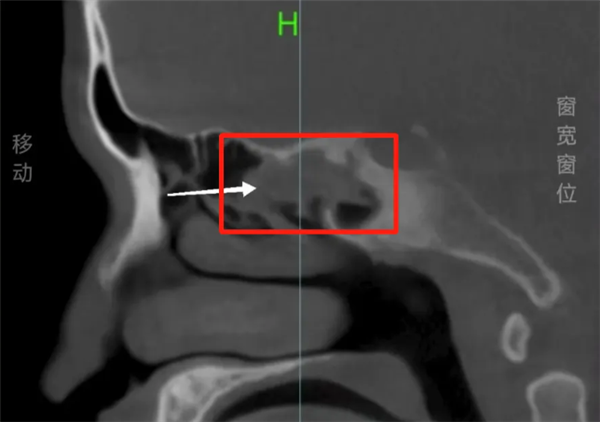

9月9日消息,据媒体报道,阿杰(化名)18年来饱受鼻塞、流脓涕的困扰,一直以为是感冒或过敏,直到今年7月到深圳大学总医院检查,才揭开真相。医生凭借经验,跳过鼻内镜直接建议CT检查,结果发现他的右侧蝶